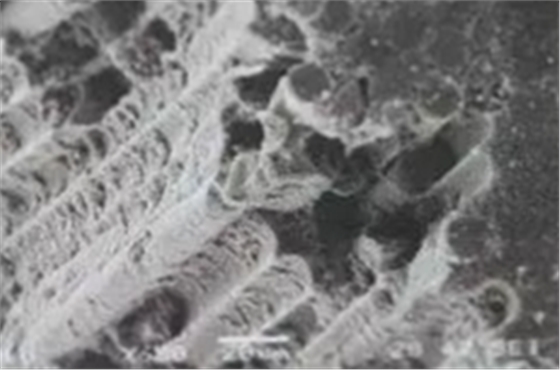

(纖維樁透光性使根管粘結(jié)劑固化充分)

(粗化和硅烷預(yù)處理)

(表面微觀結(jié)構(gòu)(SEM))

為了提高固位力,纖維樁選擇考慮到三個(gè)因素:一是透明度,二是表面處理(粗化和硅烷預(yù)處理),三是固位形態(tài)的設(shè)計(jì)。特別是纖維樁根端部分的螺紋型結(jié)構(gòu)可顯著提高樁在根管內(nèi)的機(jī)械固位,防止纖維樁脫落。